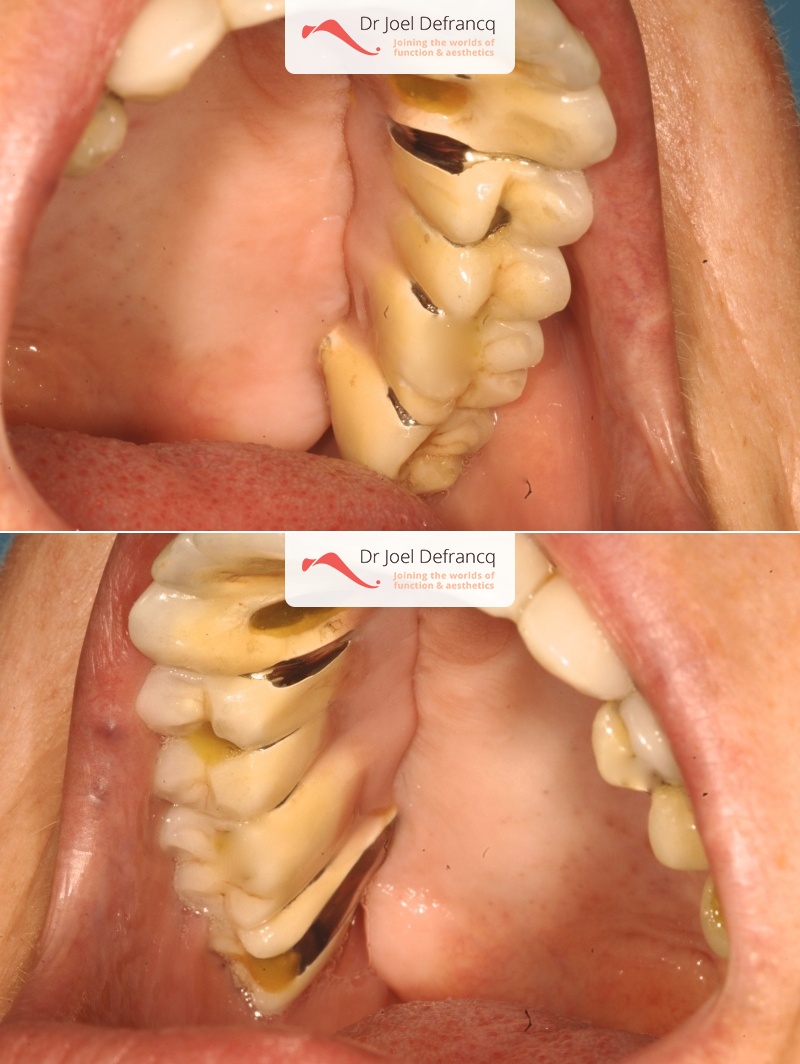

Bieke

Dentale diagnose

- Klasse I

Behandeling tandheelkundige implantaten

- Vaste tanden op implantaten (bovenkaak)